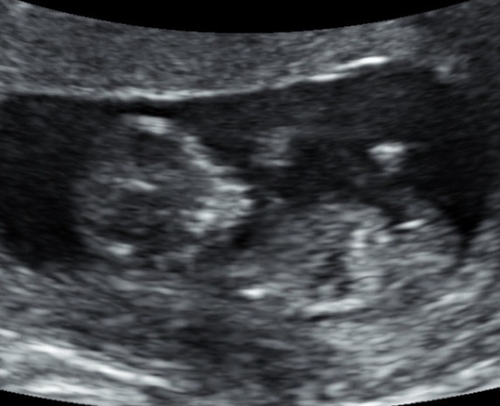

Wat denken jullie? 🎀🩵

Meisje